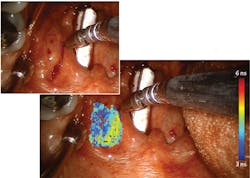

In 2010, Intuitive Surgical (Sunnyvale, CA) introduced FGS as an add-on for its da Vinci Surgical System via a module called FireFly, which uses FDA-approved indocyanine green (ICG) to provide near-infrared fluorescence (NIRF) imaging of blood flow and tissue perfusion (see Fig. 1). Released in 2000, da Vinci is used for more procedures than any other robotic surgery setup. The module is an important addition because robotic surgery removes the possibility of tactile feedback, leaving visualization as the only means of assessment. But because ICG is not a molecularly targeted probe, it lacks specificity for critical cancer assessment and cannot provide quantitative assessment of tumor margins. And the fact that ICG-based imaging requires that lights in an operating room be turned off means it does not integrate seamlessly into workflow.Searching for a more robust means of image guidance, Intuitive Surgical turned to time-resolved autofluorescence. As a label-free technique, time-resolved fluorescence spectroscopy (TRFS) relies on endogenous fluorophores as opposed to injected biomarkers, and they overcome limitations of steady-state fluorescence techniques studied for diagnosing oral cancer. The time-resolved contrast mechanism enables discrimination among fluorophores that have overlapping spectra, and it provides information about the molecular composition of tissue by revealing changes to the structural and metabolic characteristics resulting from cancer. Specifically, the approach has been demonstrated to distinguish tumors from normal tissues in head and neck cancer.

![FIGURE 1. The FireFly module for da Vinci uses indocyanine green (ICG) to provide near-infrared fluorescence (NIRF) imaging (b; white-light fluorescence is shown in [a]); the module is important because robotic surgery removes the possibility of tactile feedback, leaving visualization as the only means of assessment—but ICG-based imaging has limitations that ms-TRFS overcomes. FIGURE 1. The FireFly module for da Vinci uses indocyanine green (ICG) to provide near-infrared fluorescence (NIRF) imaging (b; white-light fluorescence is shown in [a]); the module is important because robotic surgery removes the possibility of tactile feedback, leaving visualization as the only means of assessment—but ICG-based imaging has limitations that ms-TRFS overcomes.](https://img.laserfocusworld.com/files/base/ebm/lfw/image/2019/04/1904lfw_bg_f1.png?auto=format,compress&fit=max&q=45?w=250&width=250)